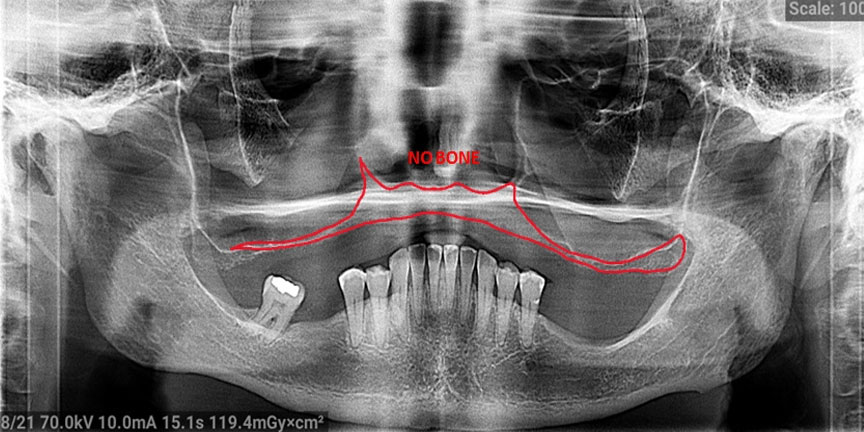

Severe Bone Loss

Difficult Cases

We treat patients when other providers cannot manage. CLICK HERE